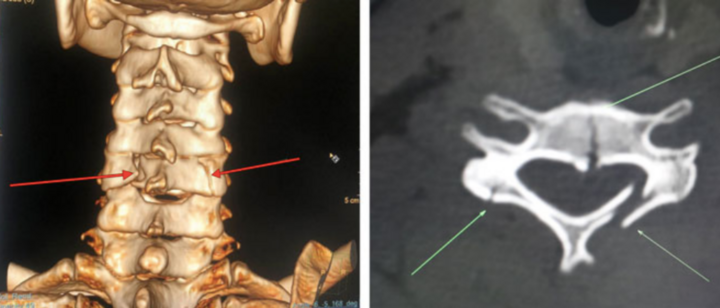

Trèo cây hái vải, chị T., 34 tuổi, bị ngã, đập vùng đầu, cổ, vai trái xuống nền đất, phải đi cấp cứu, chẩn đoán gãy vỡ đốt sống cổ.